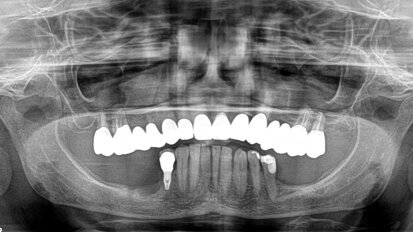

Il flusso digitale nelle riabilitazioni implanto-protesiche in chirurgia guidata

Gli impianti osteointegrati sono a oggi diventati un predicibile e valido metodo per supportare riabilitazioni protesiche, con un elevato tasso di ...